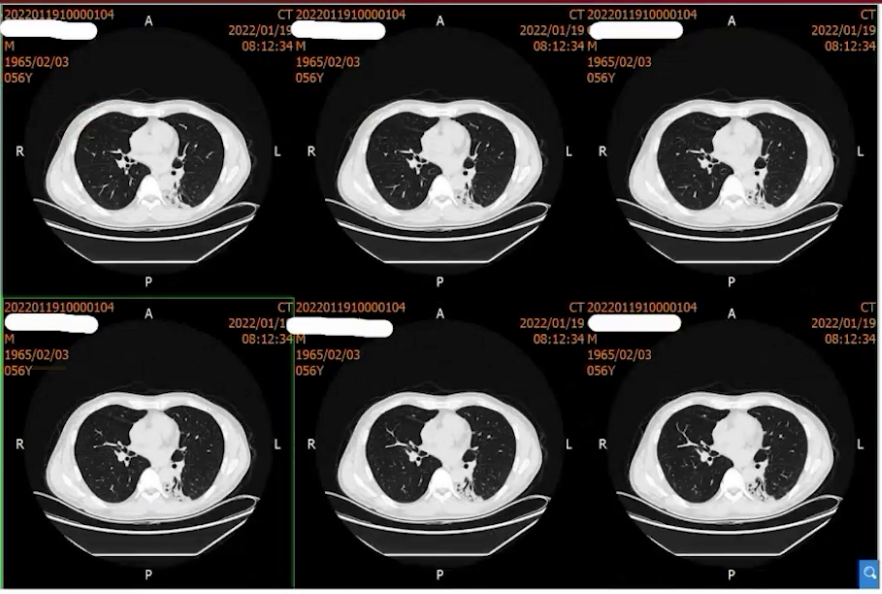

2021年10月起出现干咳伴发热(体温37.9℃),起初未重视,后咳嗽加剧伴咳白黏痰。11月15日于当地医院就诊,考虑肺炎,予青霉素联合阿奇霉素治疗一周,症状无改善。11月27日行胸部CT检查,提示左下肺斑片实变影,考虑继发性肺炎可能,给予泼尼松15mg BID一周、10mg BID一周治疗。治疗两周症状未缓解,且出现心悸气促,复查胸部CT病灶无吸收,遂自行停药,改服复方甘草合剂。两周后症状依旧,至第二家医院就诊,胸部CT显示肺部病灶增多变实,仍考虑继发性肺炎,予泼尼松30mg qd口服半月,气促稍有好转后又自行停药,期间辅以莫西沙星抗感染、乙酰半胱氨酸抗氧化治疗,复查胸部CT病灶仍无吸收,遂至我院。

胸部CTA:双侧胸廓对称,未见明显异常。双肺多发条索斑片影,左肺下叶为主。双侧肺门、纵隔、纵隔大血管和心脏影未见异常。纵隔内各组淋巴结未见异常肿大。双侧肋膈角和心膈角锐利。

治疗一个月后病灶稳定,近期复查肺部病灶已明显完全吸收。